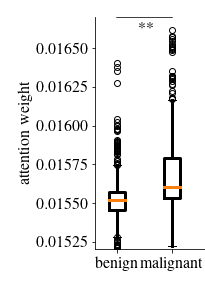

In a first analysis we use the Gleason dataset to create an artificial dataset for which the annotation per image patch is known. Each image in this dataset combines one image showing benign tissue and one image with malignant Gleason grade 5 tissue by stitching half of each together (see example in \figurereffig:fake_attention_example_img). For each image, the attention weights per patch are extracted from the MIL layer of eCaReNet. In the example it can be seen that the upper, malignant part, receives the highest attention weights, while in the benign tissue only relatively bright regions are highlighted. This may be because white regions correspond to glands, which are an important structure to distinguish benign from malignant tissue (see also \figurereffig:apd_att). A boxplot of the attention weights of all 12 example images is shown in \figurereffig:fake_attention_example_box. The attention weights for malignant patches are significantly higher than for benign patches. The original images that were stitched together are neither part of the training nor of the validation or test sets and give an unbiased estimate of importance.

Another experiment was conducted on the survival dataset. From each TMA, one image was randomly chosen from both the validation and test sets of the survival dataset, while maintaining the overall data distribution with respect to the ISUP grades, relapse time and censoring status. An expert pathologist marked tumor regions in each image, enabling us to compare this to the attention weights per patch. A patch is counted as tumorous if 66% of it lie within the marked tumor region. \figurereffig:annotation_example_img shows that all highlighted patches lie within the tumor area, however not all patches in the tumor area receive a high attention weight. \figurereffig:annotation_example_box shows the results on all images showing tumor tissue drawn from the test set. Patches marked as tumor show on average higher attention weights than non-tumor image patches.